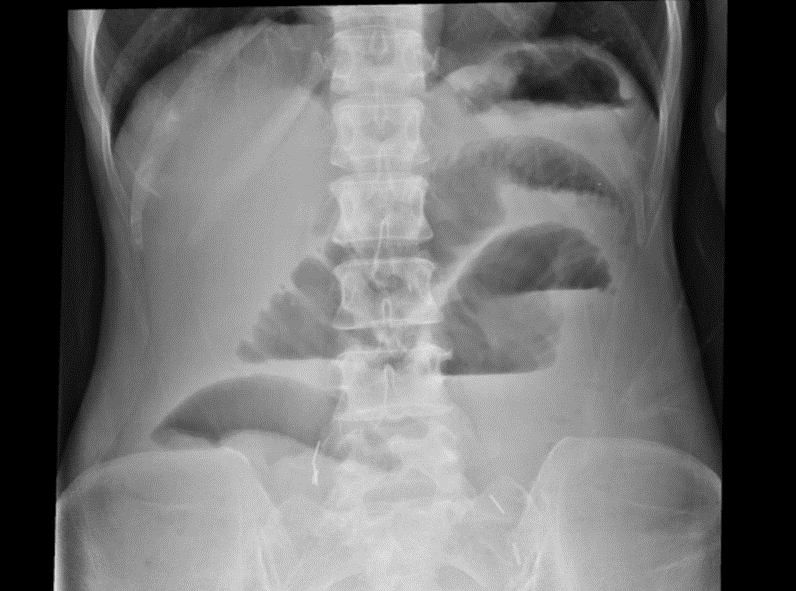

突然ですが、レントゲンクイズを出題します。画像の所見を読んで、離床の注意点を説明してください。分からないという方は、下記講座の適応あり!

[腹部画像問題の解答]

細かいひだの小腸ガスの貯留と、小腸の拡張がみられ、腸閉塞が疑われるため、離床は立ち止まり腸閉塞に対する治療・コントロールを優先すべきと考えられます。